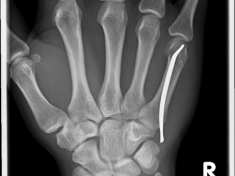

Röntgenbilder